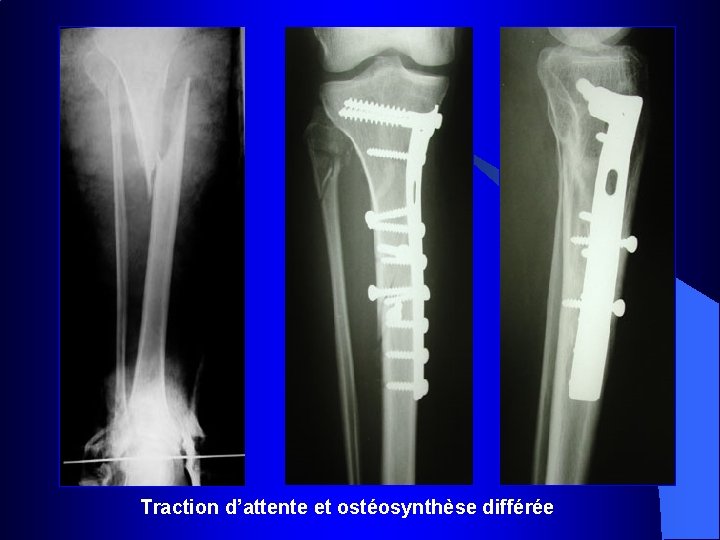

Traction d’attente et ostéosynthèse différée

Fractures comminutives

Fractures comminutives : pontage par plaques